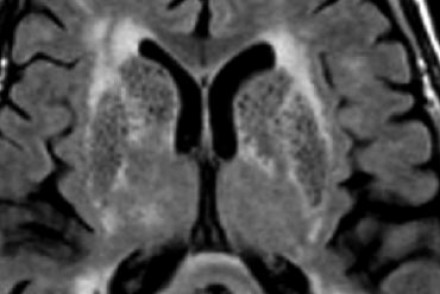

血管周圍間隙

圖片三:T2加權(quán)成像和FLAIR成像

請查看上圖并描述其病變特點。我們可以看到,在T2加權(quán)成像上,在基底節(jié)上有多個高密度病灶。在FLAIR成像上,這些病灶呈黑暗模糊影,在所有序列成像上,與腦脊液的密度相近(在T1加權(quán)成像上呈低信號)。

結(jié)合信號密度和病灶部位,可以判斷是典型的血管周圍間隙。

圖片四:FLAIR成像

血管周圍間隙是穿透軟腦膜血管周圍的腦脊液間隙。通常位于基底神經(jīng)節(jié)、腦室周圍、前連合附近以及腦干中間。在MR成像圖像上,在所有序列上的密度與腦脊液的密度相近。與其他白質(zhì)損傷病灶不同,血管周圍間隙在FLAIR和PD成像上呈黑暗模糊影,通常比較小,位于前連合附近的除外,此處的血管周圍間隙比較大。

在上圖中,我們可以看到比較寬的血管周圍間隙和在白質(zhì)中有融合的高密度信號病灶。該圖像很好的顯示了血管周圍間隙和白質(zhì)損傷病灶之間的差異。

由于周圍結(jié)構(gòu)組織的萎縮,血管周圍間隙會隨著衰老和高血壓而逐漸增寬。